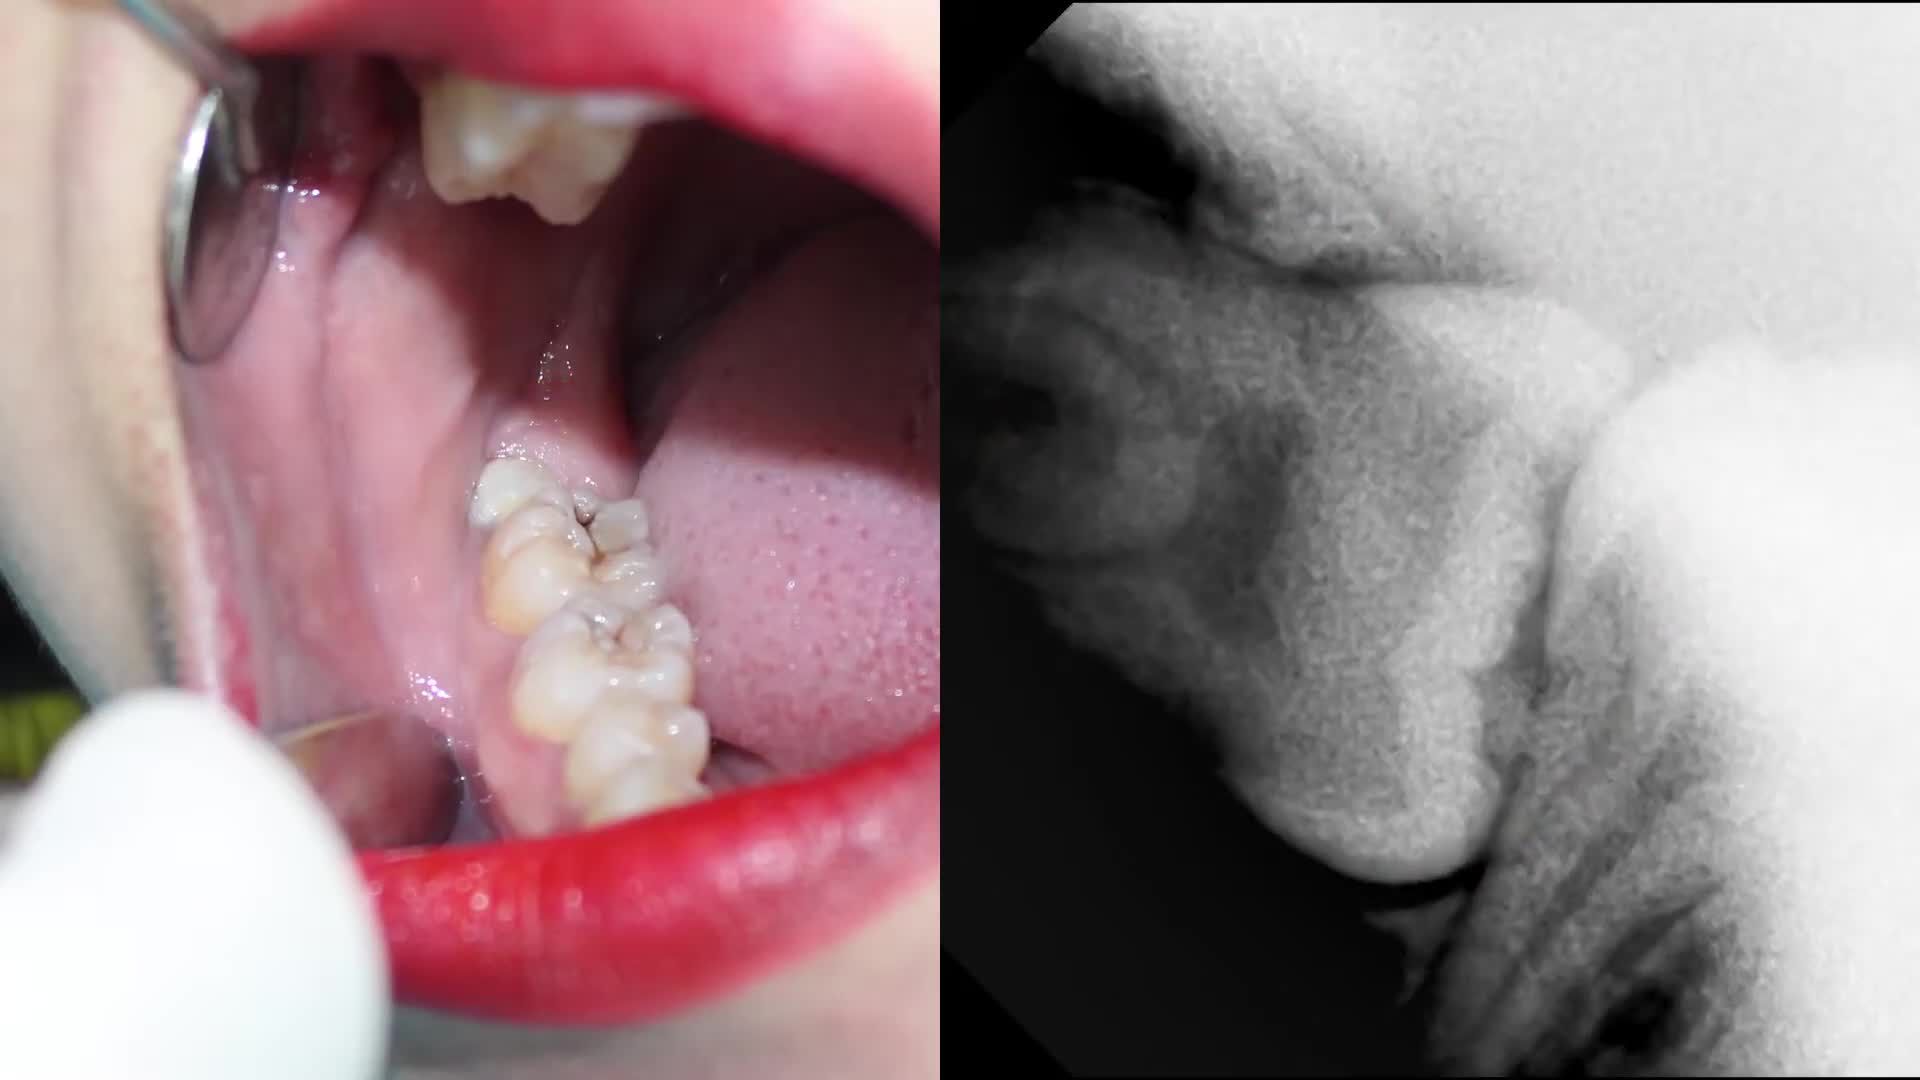

? Chị M.Hằng (24 tuổi, quận 10) có 3_răng_khôn. Lần đầu tiên đến nha khoa Đông Nam, chị đã được bác sĩ xử lý nhanh gọn cùng lúc răng khôn hàm trên và hàm dưới bên phải bị mọc lệch, lợi trùm.

? Và đây là lần thứ 2 chị quay lại nha khoa để nhổ bỏ chiếc răng còn lại.

➖ Dựa vào kết quả chụp phim, chiếc răng khôn lần này mọc nghiêng 90 độ trong xương hàm, đâm vào chân răng số 7 bên cạnh làm chiếc răng này bị sâu.

➖ Theo chỉ định của bác sĩ, sau khi nhổ răng khôn hoàn tất, vết thương ổn định sẽ tiến hành điều trị chiếc răng số 7 để bảo tồn răng thật.